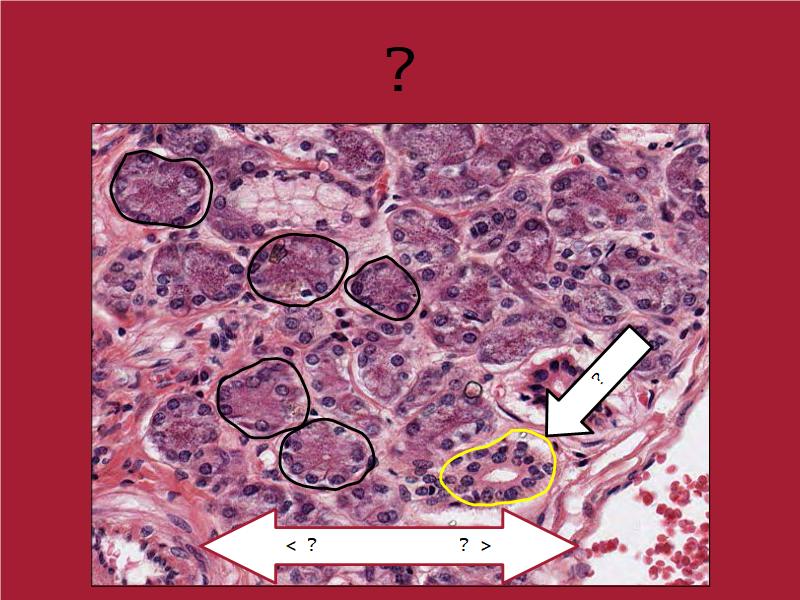

Mammary gland

Write short notes describing the structure of the mammary gland.

(5)

Mammary gland

- Compound tubuloalveolar gland

- 12 - 20 glands

- Each with own lactiferous duct

- Each with own lactiferous sinus

- Opens on skin at apex of nipple

Two stages

- Resting

- Active

Resting and active

Describe the resting mammary gland and compare with the active gland.

(8)

Resting gland

- Connective tissue dominate

- More adipose tissue

- Glandular tissue reduced

Active gland

- Terminal ducts expand

- Forms alveoli

- Connective tissue reduced

- Adipose tissue reduced

- Glandular tissue dominate

Structures

List the structures and cells found in the mammary gland.

Structures

- Lactiferous sinuses

- Stratified squamous near opening on skin

- Stratified cuboidal other parts

- Lactiferous ducts

- Stratified cuboidal

- Myoepithelial cells

- Underlie lactiferous ducts in most areas

- Basal lamina

- Separate epithelial components from stroma

Active gland

- Much larger than resting phase

- Terminal ducts proliferate to form alveoli

- Alveoli

- Surrounded by incomplete myoepithelial cells

Alveolar cells

- Apocrine secretion

- Active state

- Resting state